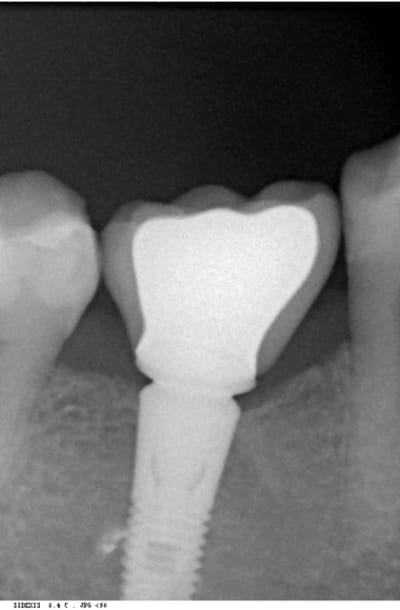

bon les pièces jointes d'alhoun.

décidément aussi nul en endo qu'en internet, et ton implant il est de traviole;)

dans la même philosophie de connectique

Easyimplant mjxotp - Eugenol

Rvg easy briwxo - Eugenol

Ok j'ai compris. Par contre, sur la radio l'implant a l'air d'être conique sur toute sa hauteur, c'est une illusion d'optique où il est vraiment comme ça, je ne le vois pas sur le site d'Astra ?

tu parles de celui de growler?

c'est normal c'est pas un astra, c'est un easy implant, mais il est pas conique tout le long il me semble.

çà doit être une déformation du cliché, regardes bien le premier cliché avec le pilier de cicatisation: on voit bien la partie cylindrique puis l'évasement.

Easy master l gmp7su - Eugenol